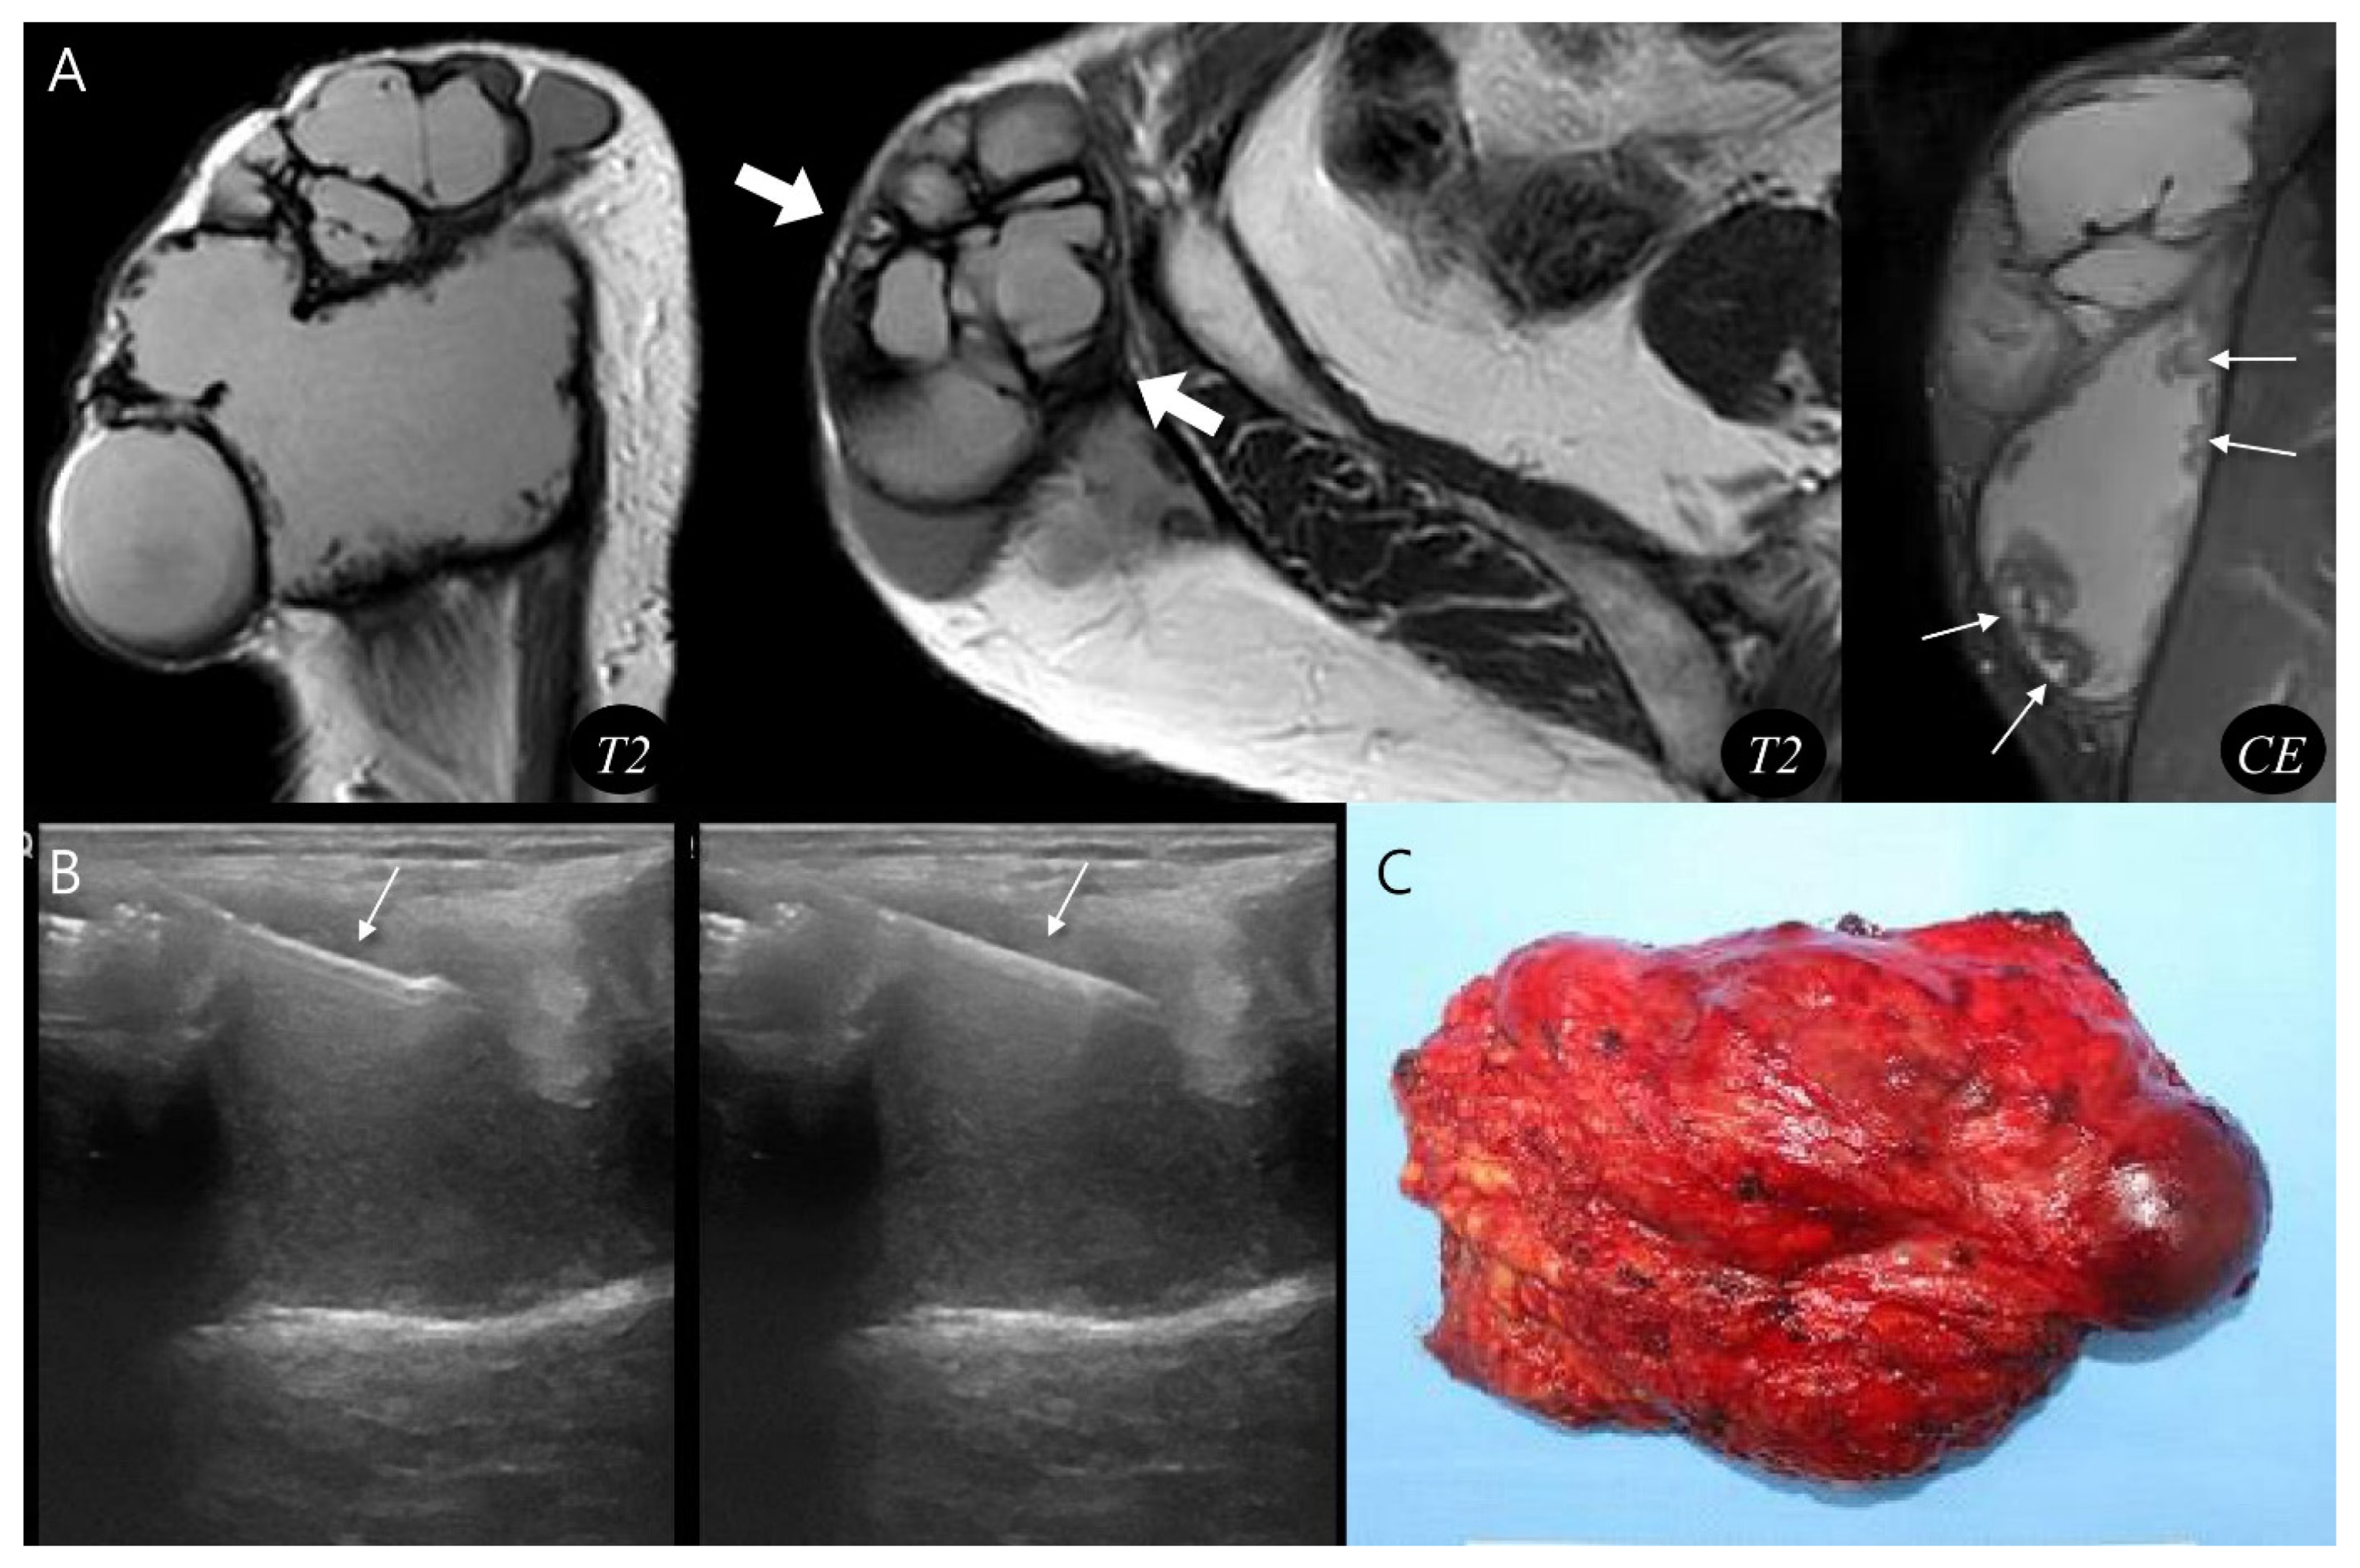

Using the proposed diagnostic flowchart, we successfully applied this approach in representative cases. In a representative pseudoaneurysm case (Figure 3), the hematoma-like lesion demonstrated a central flow void with adjacent neurovascular bundle involvement on MRI, which allowed a confident diagnosis of pseudoaneurysm; the patient subsequently underwent successful endovascular embolization. In contrast, in a CEH case (Figure 4), the lesion exhibited a multilobular hematoma-like lesion with internal septations and lacked neurovascular bundle involvement, findings that favored the diagnosis of CEH and were later confirmed after wide surgical excision. These representative cases underscore the practical utility of the flowchart by illustrating how specific imaging features can be translated into accurate diagnostic decisions and directly guide appropriate therapeutic strategies.

Figure 4.

Diagnosis and treatment of chronic expanding hematoma. (A) Sagittal and axial T2-weighted MR images demonstrate a multilobular, subcutaneous mass (thick arrows) with internal septations. The lesion shows peripheral nodular enhancement (thin arrows, granulation tissue) on coronal T1-weighted contrast-enhanced MR image. (B) Ultrasound-guided biopsy was performed using a core needle (arrows), confirming the hematoma. (C) Gross photograph of the wide excision demonstrates chronic expanding hematoma.